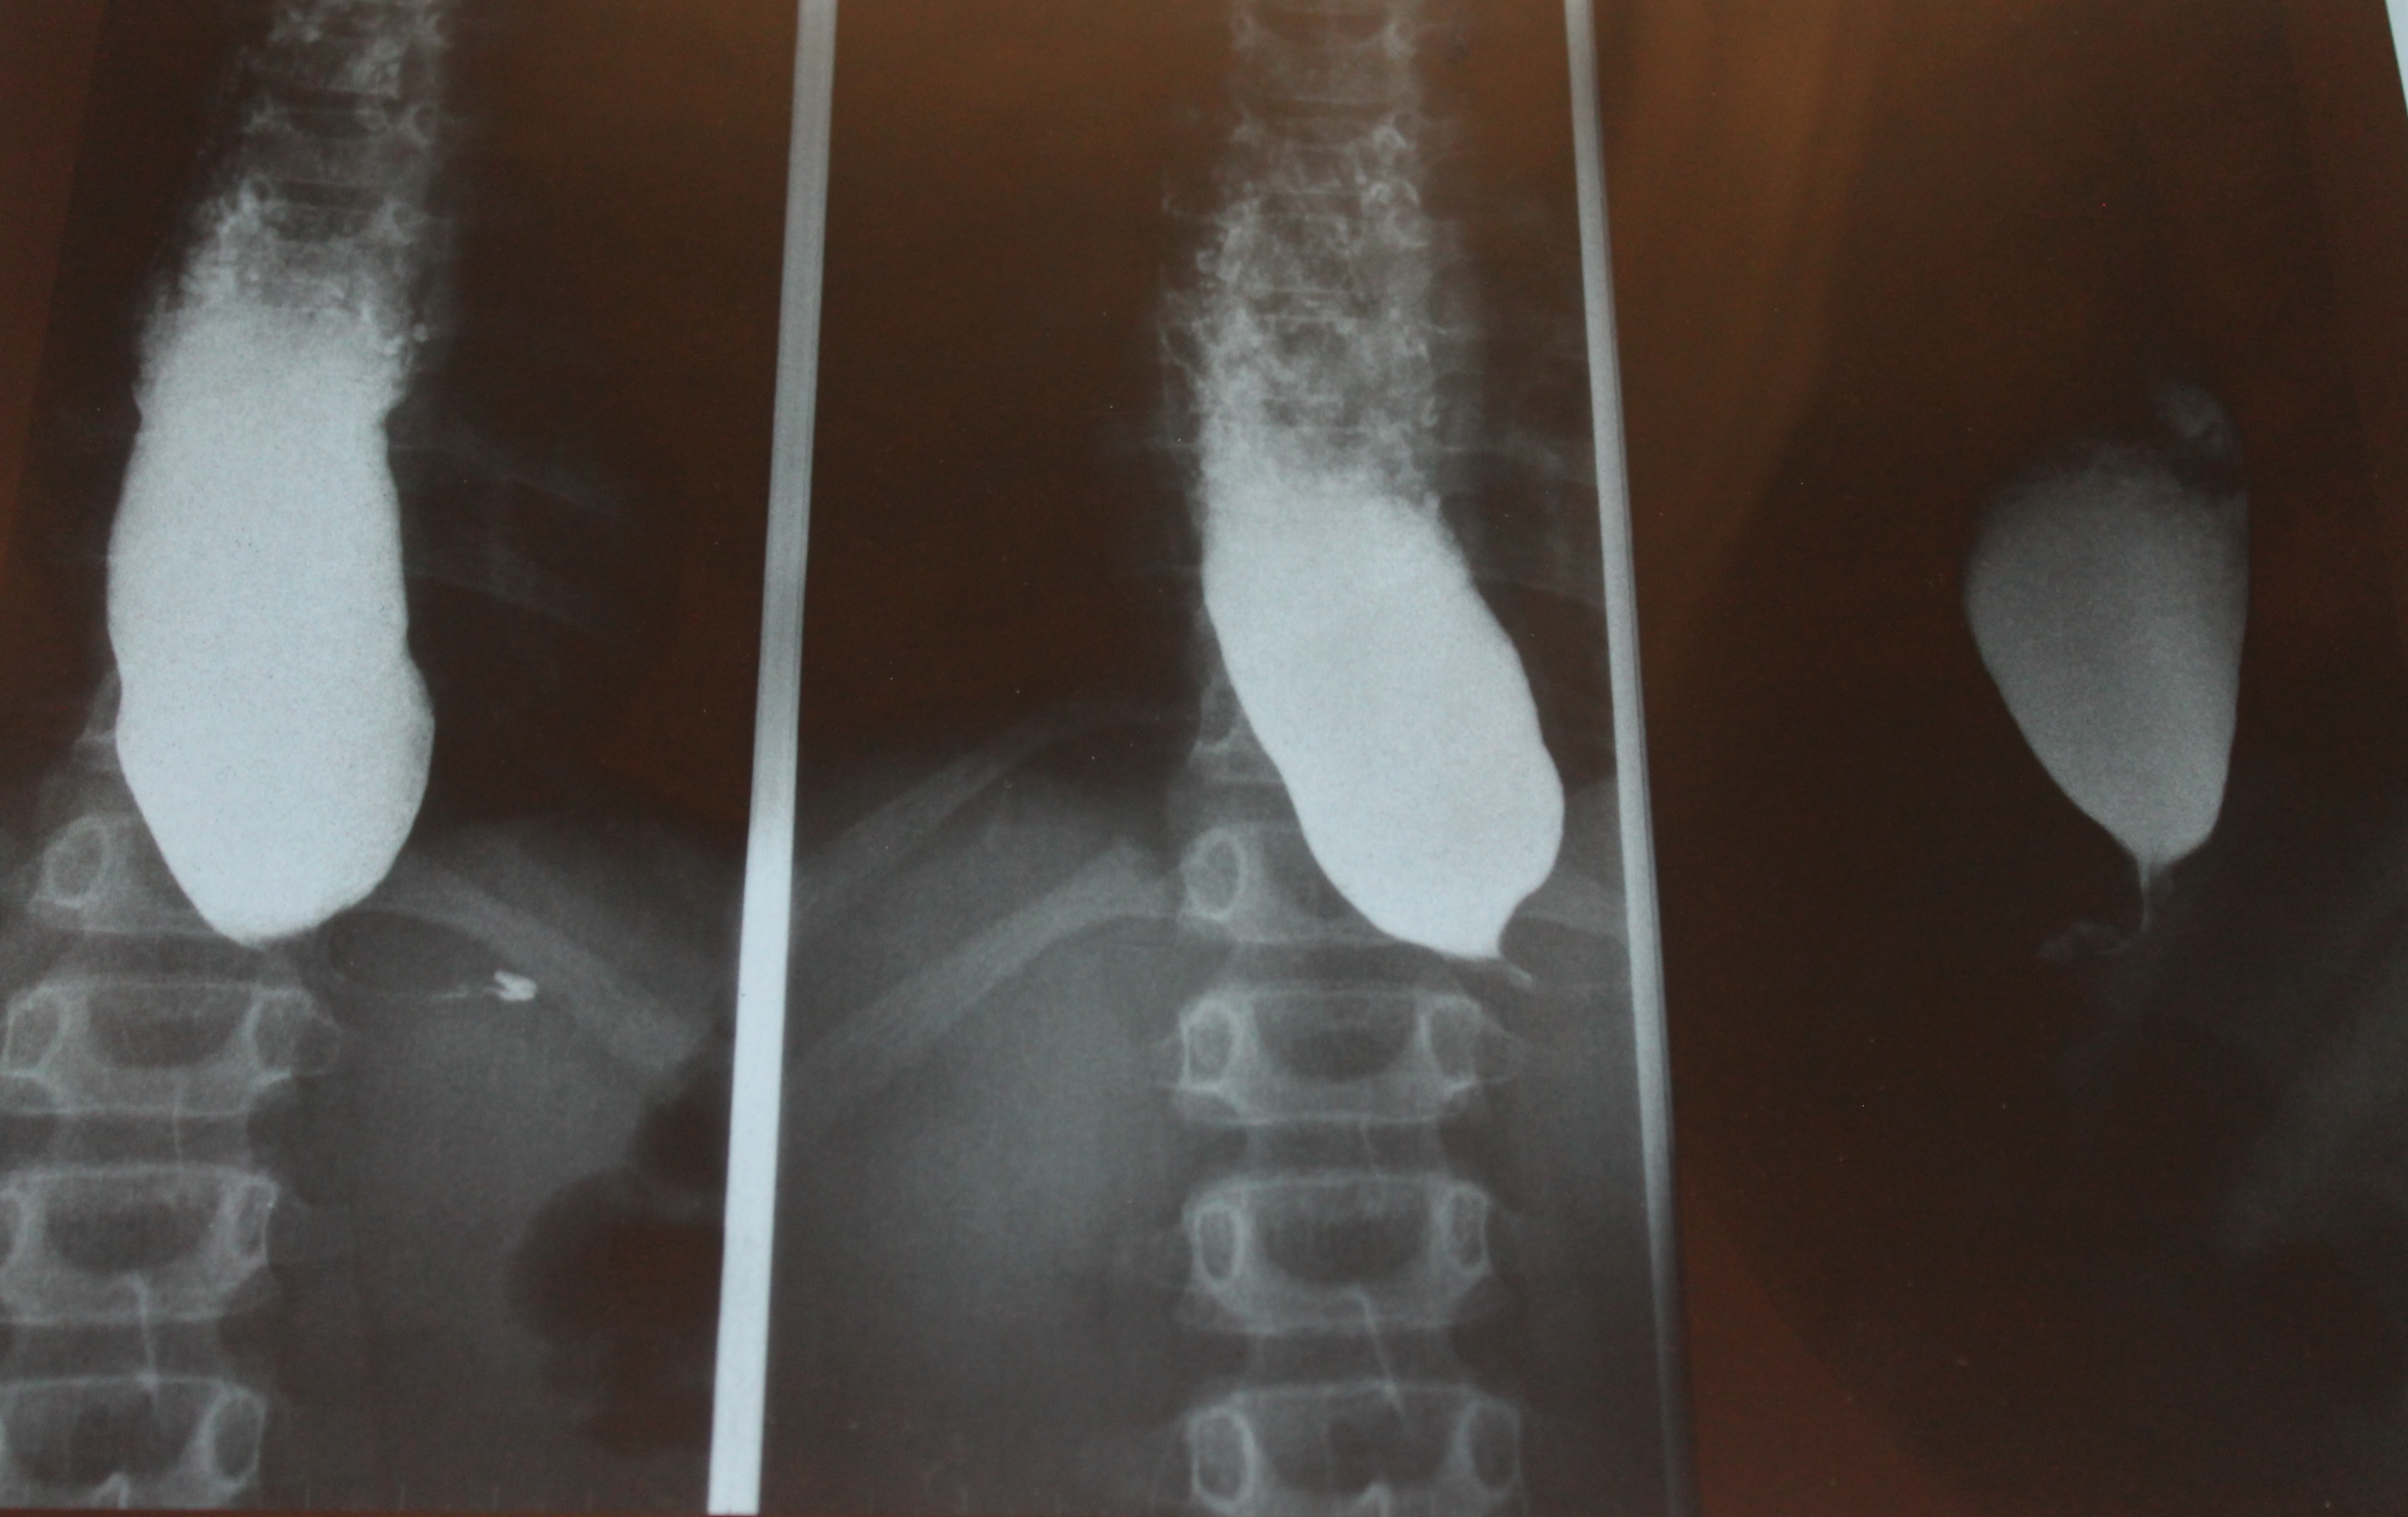

El tránsito digestivo fue sugestivo de acalasia. Se informó como engrosamiento esofágico y stop en su tercio distal. Tras posición en bipedestación, persiste la estenosis distal del esófago sin presencia de paso a la cavidad gástrica. Se aspira el contenido tras la exploración.